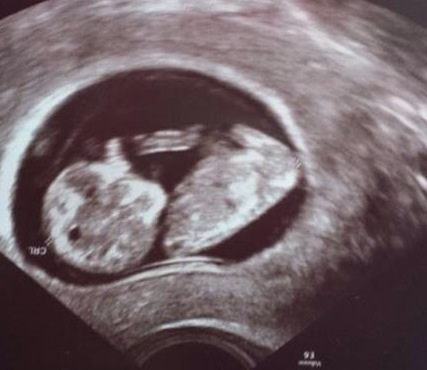

I will give you more details of her family make up in 48 hours. Please give her lots of guesses. She is between 11-12 weeks so still early to guess. I'll post her next scan in a couple of weeks too..